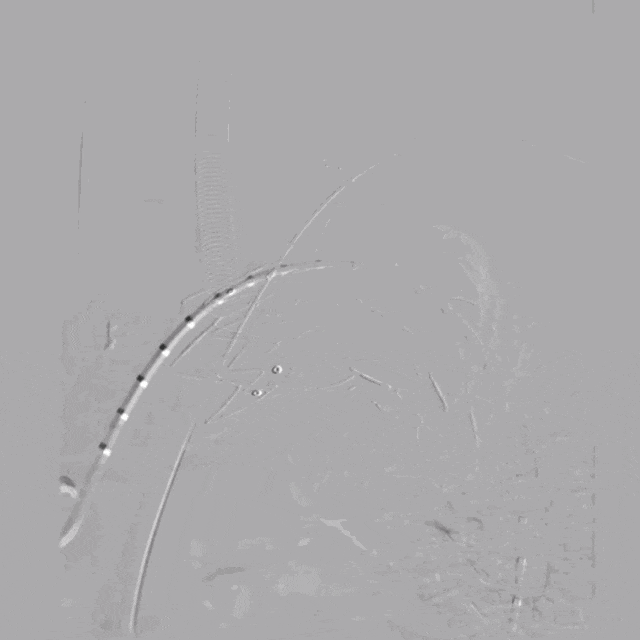

4. 依次导入球囊3mm*30mm、6mm*40mm至开窗口行扩张并再次确认导丝头穿过主动脉支架覆膜。

泥鳅导丝怎么用符伟国/王利新教授团队:0.035"普通泥鳅导丝进行胸主动脉弓上分支原位开窗的病例分享_https://www.jmylbn.com_新闻资讯_第17张

使用3mm*30mm球囊扩张窗口,改变DSA角度证实破膜成功

泥鳅导丝怎么用符伟国/王利新教授团队:0.035"普通泥鳅导丝进行胸主动脉弓上分支原位开窗的病例分享_https://www.jmylbn.com_新闻资讯_第18张

进一步使用6mm*40mm球囊扩张开窗口